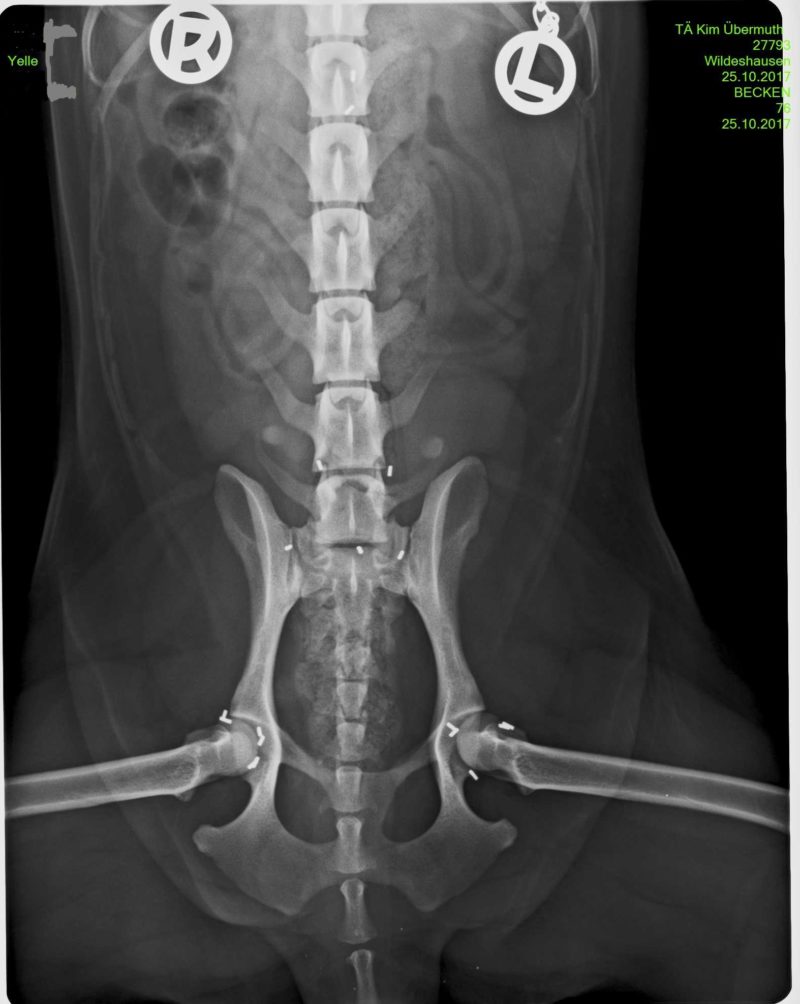

Wir arbeiten mit dieser modifizierten Methode, die als ganzheitliche Orthopädie zu verstehen ist, seit nunmehr 16 Jahren erfolgreich in unserer Praxis. Die vorhergehende umfassende Diagnostik mit einer ausführlichen Gangbildanalyse und der Triggerpunktdiagnostik (Schmerzpunktuntersuchung) erfasst alle relevanten Schmerzen, auch die, die sich nur aus der Entlastung der veränderten Gelenke und damit einer Überbelastung in die anderen Gelenke ergeben. Weiterführend werden digitale Röntgenbilder angefertigt.

In der Gangbildanalyse wurde die Lahmheit hinten links und vorne rechts bestätigt. Cash lief sehr schwerfällig und zeigte eine deutliche Hüftrotation auf der rechten Seite. Die Ellenbogen waren beide stark ausgestellt und Cash schleift über die Vorderfüße. Ein Schwingen im Rücken lässt Cash nicht zu und hält sich in der Rückenmuskulatur sehr fest. Die Untersuchung der Triggerpunkte war für Cash besonders im Rücken, an den Hüften, den Knien und den Ellenbogen sehr unangenehm. Nach der Blutuntersuchung, die keine Abweichungen ergab, und der folgenden in einer leichten Sedation ausgeführten ausführlichen Röntgendiagnostik wurden alle Befunde (beidseits hochgradige HD, hochgradige Ellenbogenarthrose rechts und links, Knie links post OP) und die mögliche Prognose für Cashs Schmerzbehandlung besprochen. Die Besitzer entschieden sich für eine Goldakupunkturbehandlung ihres Hundes.

Vor einem Monat wurde uns „Yelle“, eine 4-jährige Cocker-Spaniel-Hündin, vorgestellt. Durch die Gangbildanalyse, der Untersuchung der Triggerpunkte und das folgende Röntgen wurde schnell klar, dass Yelle durch eine sehr lose schmerzhafte Hüfte ein deutlich verändertes Gangbild zeigte. Die Besitzer entschieden sich daher frühzeitig für eine Goldakupunktur, um Folgeschäden an den anderen Gelenken zu minimieren. Die Kontrolluntersuchung nach der Goldimplantation verlief sehr positiv - Yelle will spielen und toben. An diesem Punkt ist es wichtig, dem Muskelaufbau Zeit zu geben und den Hund noch nicht zu viel toben zu lassen. Eine geregelte Bewegung und eventuelle physiotherapeutische Unterstützung hilft, das Gangbild zu stabilisieren.